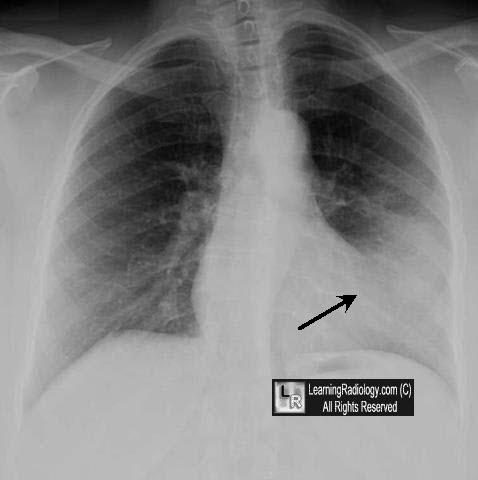

نضع بين ايديكم مجموعة الصور الاضافية على السلايدات التي تم شرحها في X-ray session :

pneumothorax

Hydrothorax

silhouette sign singular